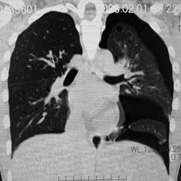

臨床的には進行性肺嚢胞化, くり返す肺気腫, 乳び性胸水貯留が特徴で, 多くの症例では進行性に呼吸不全となる*1

LAM患者さんに認められた両側肺気腫(右図:胸部CT)

初診時CT(左)から2年後のCTでは肺の嚢胞化が著明となっている。